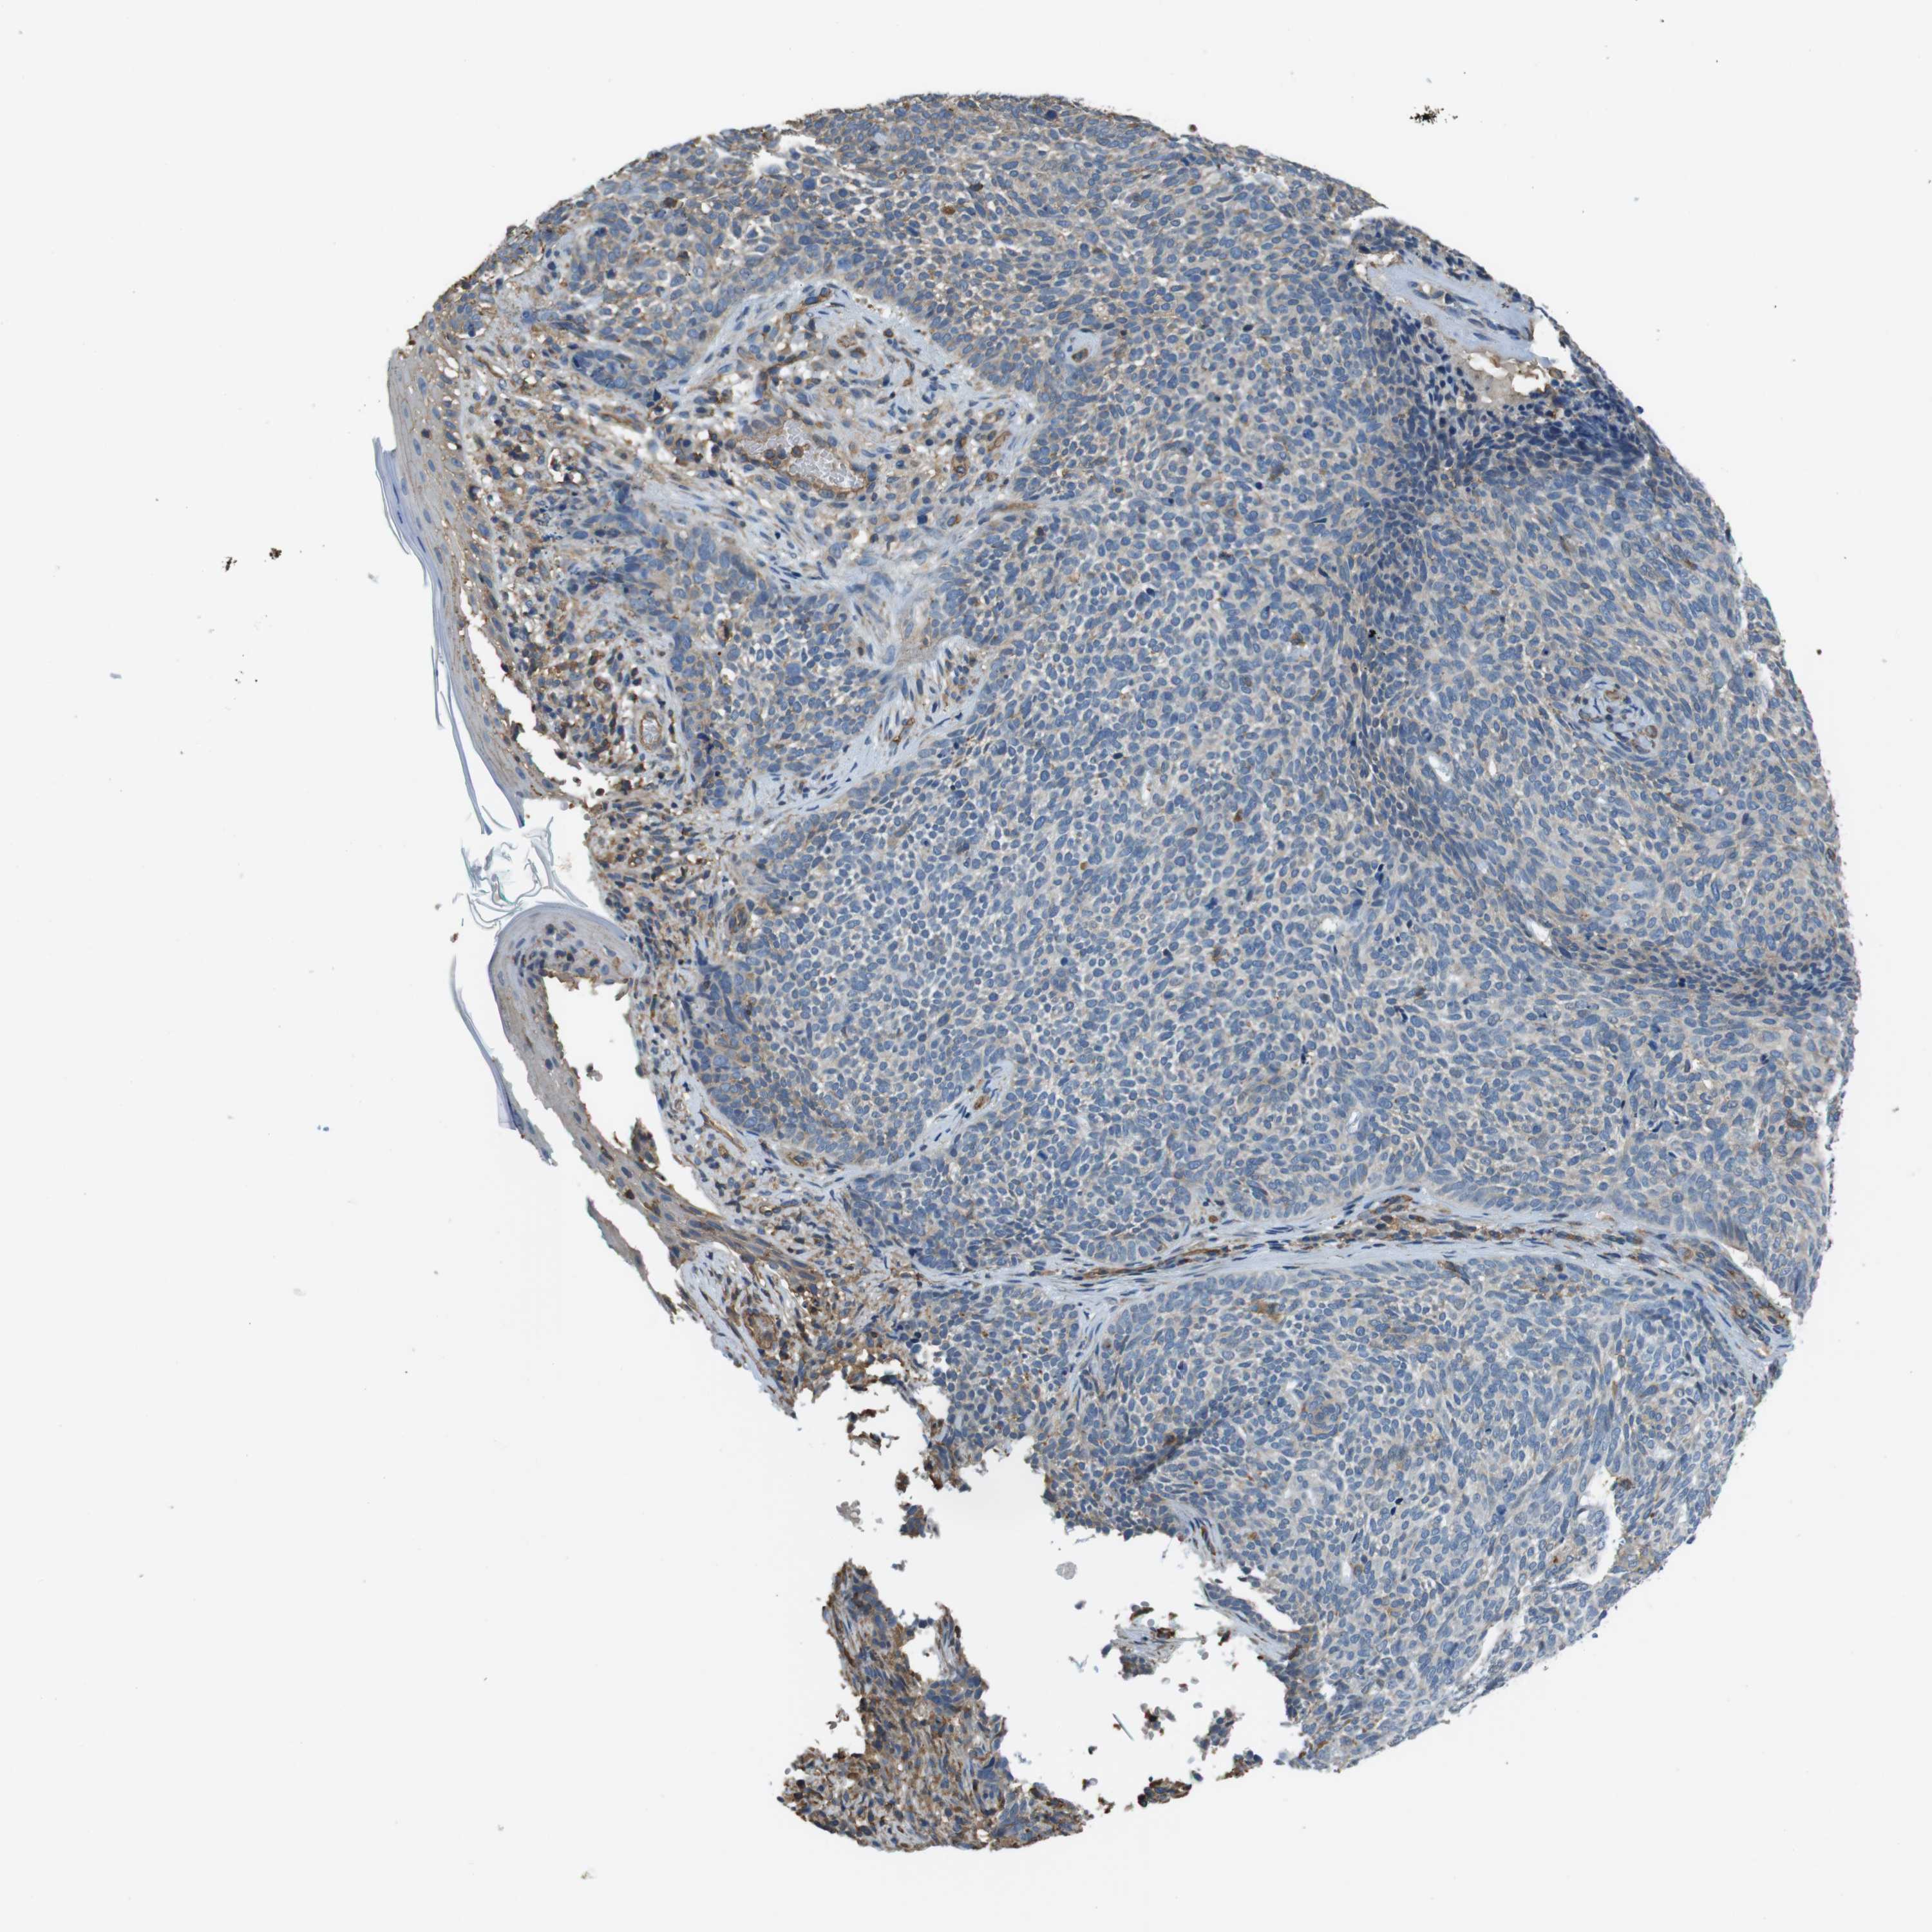

SKIN CANCER - Protein expressioni

A mouse-over function shows sample information and annotation data. Click on an image to view it in a full screen mode. Samples can be filtered based on level of antibody staining by selecting one or several of the following categories: high, medium, low and not detected. The assay and annotation is described here.

Antibody stainingi

Antibody staining in the annotated cell types in the current human tissue is reported as not detected, low, medium, or high, based on conventional immunohistochemistry profiling in selected tissues. This score is based on the combination of the staining intensity and fraction of stained cells.

Each image is clickable and will lead to virtual microscopy that enables deeper exploration of all samples and also displays staining intensity scores, fraction scores and subcellular localization as well as patient and tissue information for each sample.

Antibody HPA014050

Staining

High

Medium

Low

Not detected

Intensity

Strong

Moderate

Weak

Negative

Quantity

>75%

75%-25%

<25%

None

Location

Nuclear

Cytoplasmic/membranous

Cytoplasmic/membranous,nuclear

Squamous cell carcinoma, NOS

Basal cell carcinoma

Adnexal tumor, benign